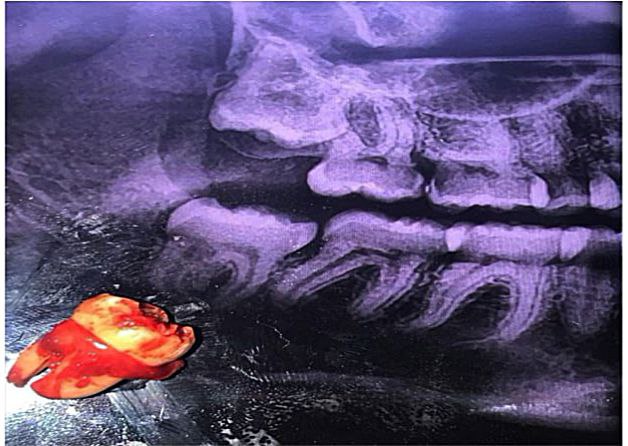

أجراء عملية قلع سن مطمور بالفك السفلي لمريض زار عيادة جراحة الفم